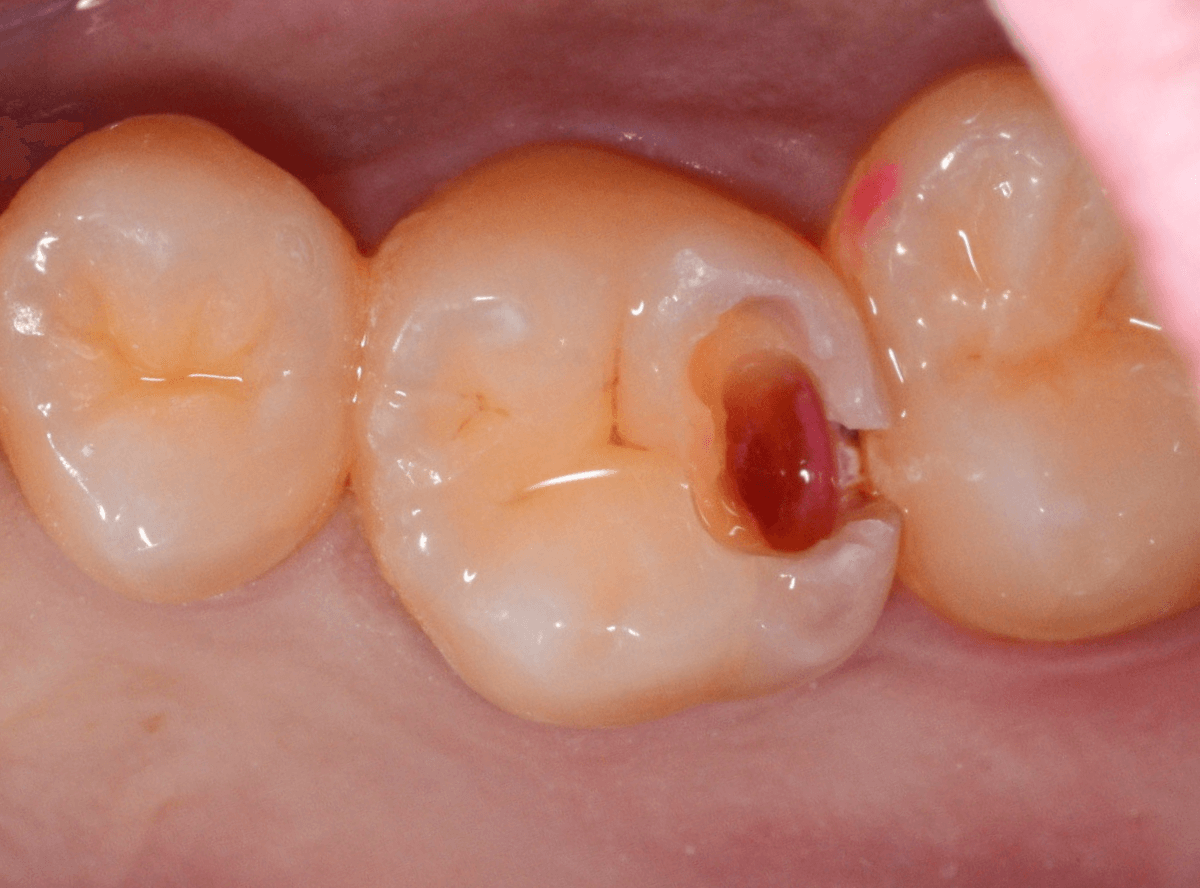

Case.2 症状がないけど、神経が見えるほどの虫歯!

こちらも別の歯の治療を目的に受診された方です。

特に症状もないため、本人には全く自覚はありませんが、一目見てわかるほど歯と歯の間に大きな虫歯があります。

治療をすると、やはり大きな虫歯が出てきました。

まだまだ虫歯は深いです。

かなり大きく削りましたが、まだ虫歯が残っているのがわかります(赤く染まっている部分)。

慎重に虫歯を除去し、神経ギリギリのところで虫歯をくいとめました。

しかし、手前の歯をよく見ると、神経がうすく透けて見える状態ですので、本当にギリギリです。

このような深い状態の虫歯でも、症状がなく、治療後に痛み出す事もあります。